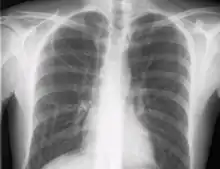

خلال قسطرة اوردة ما تحت الترقوة، المقسطر قد يدفع بالخطأ إلى الأوردة المحيطة بالرقبة على نفس الجهة بدلاً من الجزء العلوي من الوريد الأجوف.صورة سينية للصدر تؤخذ بعد إدخال القسطار لإبعاد احتمالية خروج القسطار عن مكانة.[18] أيضاً يمكن لرأس القسطار أن يوجه خطأً إلى الجزء الأخر من الجسد، الأوردة ما أسفل الترقوة في الرقبة، بدلاً من التعامل مع الجزء العلوي من الوريد الأجوف.

بعد ذلك يتم إدخال القسطار عن طريق استخدام تقنية سيلدنجر: يمر أنبوب موجه رفيع من خلال الإبرة وبعد ذلك يتم إخراج الإبرة. ربما يستخدم جهاز موسع يمر فوق الأنبوب الموجه من أجل توسيع المجرى. أخيراً يمر القسطار بنفسه من فوق الأنبوب الموجه الذي يتم إخراجه بعد ذلك. تشفط جميع تجاويف القسطار (من أجل التأكد بأنه تم وضعها داخل الوريد) ويتم مسحها بممحلول ملحي أو هيبارين. عادةً يتم عمل أشعة سينية للصدر بعد العملية للتأكد بأن القسطار موضوع بداخل الوريد الأجوف العلوي وبأنه لم يحدث استرواح صدري من دون قصد. يمكن استخدام أنظمة وضع الأوعية الدموية للتأكد من وضع الطرف أثناء الإدخال.